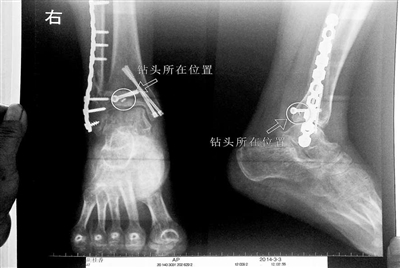

胡女士的腿部X光圖

近日,在豐臺區(qū)右安門醫(yī)院,北京青年報記者見到了胡女士,她走起路來顯得一瘸一拐,腿腳并不利索。在她帶來的X光片上,可以清晰地看到,有一個異物存在于腿內(nèi)部。

“我當(dāng)時就嚇蒙了,怎么會有一個鉆頭在骨頭里?”胡女士余悸未消地說,第二天拍攝的X光片顯示,2厘米左右的鉆頭遺留在她右腳腳踝上部的骨頭內(nèi)。

胡女士說,當(dāng)時旁邊的醫(yī)生勸慰自己,稱鉆頭留在腿里并不會有什么問題。出院后,胡女士每個月都會來醫(yī)院做復(fù)查,拍X光片。她說,每次都能夠清晰地看見自己骨頭里的那個明晃晃的“小東西”。

“按照照片里的位置,相對來說是沒有害的?!必S臺區(qū)右安門醫(yī)院醫(yī)務(wù)科徐主任告訴胡女士,任何事情都無法做出絕對的判斷,但是從目前情況而言,鉆頭對于腿部沒有更多的危害。她介紹說,臨床上遇到過很多這種情況,諸如鋼板釘子,有時候釘子滑扣,無法取下,也只能存在體內(nèi),但是這些都是個別情況。

“留在她腿里的鉆頭確實無法取出。”徐主任解釋說,按常理說,鉆頭不應(yīng)該斷在里面,但現(xiàn)在事情確實發(fā)生了。鉆頭沒有折在關(guān)節(jié),而是在跖骨內(nèi),跖骨主要起支撐作用,不像關(guān)節(jié)那樣起活動作用,而且這個部位比較質(zhì)密,并非像肌肉要經(jīng)?;顒邮艿綌D壓。